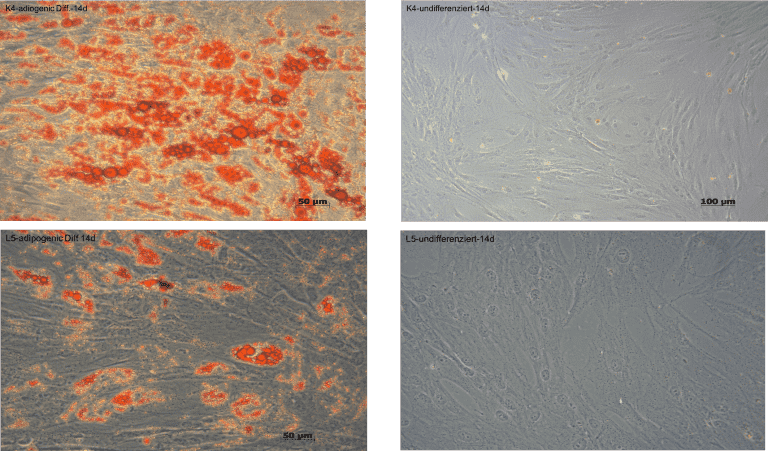

Das Lipödem ist nach der Definition der S1 Leitlinie AWMF eine chronisch progrediente Erkrankung, die nahezu ausschließlich bei Frauen auftritt und durch eine Fettverteilungsstörung mit deutlicher Disproportion zwischen Stamm und Extremitäten gekennzeichnet ist.

Diese entstehen aufgrund einer umschriebenen, symmetrisch lokalisierten Unterhautfettgewebsvermehrung. Zusätzlich bestehen Ödeme, die durch Orthostase verstärkt werden, sowie eine Hämatomneigung nach Bagatelltraumen. Charakteristisch ist eine gesteigerte Druckschmerzhaftigkeit, meist bestehen Spontanschmerzen. Die Ursache des Lipödems ist bisher unbekannt. Eine genetische Komponente wird aufgrund von positiven Familienanamnesen angenommen. Die erkrankten Fettzellen lassen sich nicht durch Sport oder Ernährungsmaßnahmen beeinflussen. Eine fehlende Transportfähigkeit der Lymphgefäße führt sekundär zu einem Stau an lipid-und proteinreichen Substanzen rund um die Adipozyten. Da der Abtransport nicht gewährleistet ist, kommt es zu einer vermehrten Ansammlung ebenfalls in den Adipozyten. Sekundär entwickeln sich in höheren Stadien ein chronisches Lymphödem und eine Fibrosierung der Adipozyten. Die charakteristische Fettverteilungsstörung der erkrankten Adipozyten lassen sich an den Extremitäten erkennen durch das Aussparen von Händen und Füßen, sowie einem typischen „Säulenbein“ und verstrichenen Konturen. Kennzeichnend für ein Lipödem ist außerdem die Gefäßfragilität, die sich durch ein leichtes Auftreten von Hämatomen bei inadäquatem Druck oder Berührung der Extremitäten ergeben. Des Weiteren klagen die Patientinnen meist über Ruheschmerzen in den Beinen, vor allem nach längerer Belastung. Die konservative Therapie mittels Kompressionstherapie und manueller Lymphdrainage beschränkt sich auf die symptomatische Linderung.

Die einzige nachgewiesene Therapie des Lipödems ist die radikale zirkuläre Liposuktion, die mit überdurchschnittlich hohen Kosten einhergeht und von den Krankenkassen in der Regel nicht übernommen wird. Diese Form der Therapie zeigte in Langzeitstudien eine Wiederherstellung einer hohen Lebensqualität und kaum Rückfallquoten. Aktuell gibt es eine unklare Studienlage zur Pathogenese des Lipödems und kaum Forschung zur molekularen Ätiopathogenese. Ziel dieser Studie ist es daher, die molekularbiologische Pathogenese dieses Krankheitsbildes zu erforschen und die Adipozyten in vitro Kultur auf unterschiedliche Faktoren zu untersuchen. Alle für die Studie ausgewählten Patientinnen leiden an Lipödem vom Ganzbeintyp (nach Herpertz) im Stadium II Grad II (nach Fife, Meier-Vollrath). Die Vergleichsgruppe wird von Patientinnen ohne diagnostiziertes Lipödem gebildet, deren Fettzellen durch die gleiche Liposuktionsmethode gewonnen werden.

Die Studie wird in Kooperation mit der Praxis Dr. Dominik von Lukowicz durchgeführt, der sich als Facharzt für Plastischen und Ästhetische Chirurgie auf die Behandlung des Lipödems spezialisiert hat und über jahrelange Erfahrung im Bereich der speziellen Liposuktion bei Lipödem verfügt.

normales Fettgewebe I Lipödem-Fettgewebe